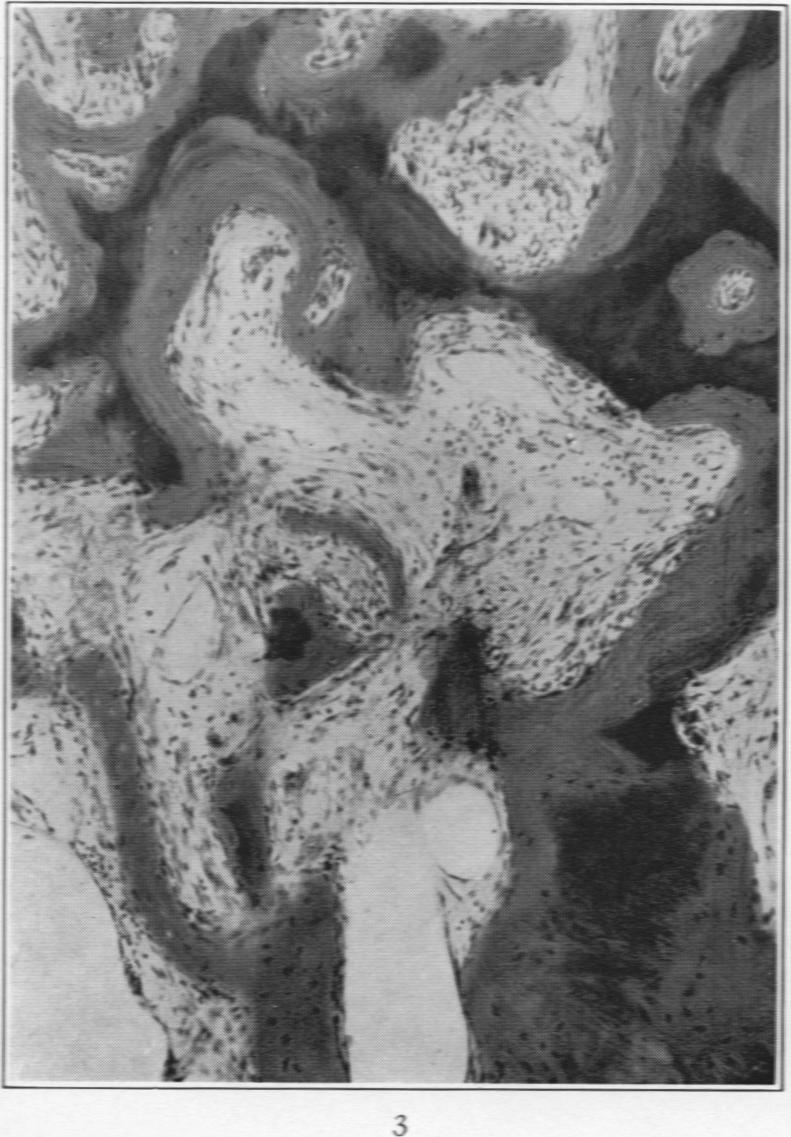

Osteitis Fibrosa.

Am J Pathol. 1932 May;8(3):263-270.3.